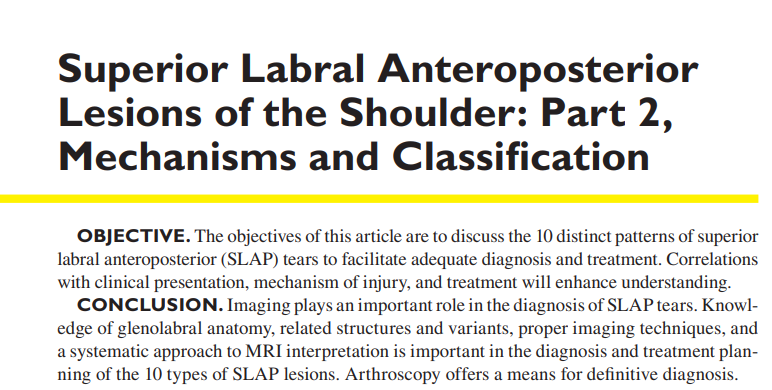

- SLAP 병변은 이 중에서 어깨 관절 와순의 손상입니다. 관절와순에서도 이두근 장두 힘줄이 관절와순과 연결된 부위와 연관되어 발생합니다.

- 손상부위는 보통 10시~2시방향에 위치합니다.

- 방카르트 병변(Bankart lesion)이나, ALPSA(anterior labroligamentous periosteal sleeve avulsion) 병변과는 다르게 어깨 불안정성과는 관련이 적습니다.